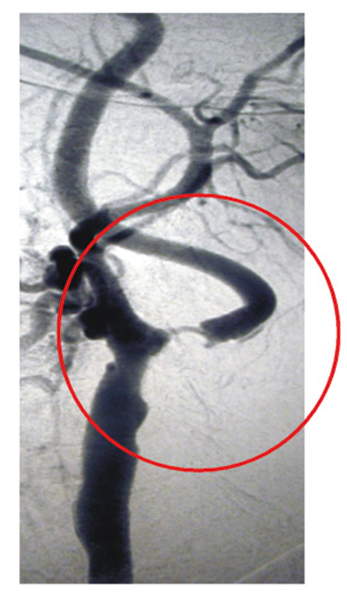

Man unterscheidet drei Typen von Gefährdungen:

Für Schlaganfälle der kleinen Gefäße ist vor allem ein zu hoher Blutdruck verantwortlich.

Schlaganfallprophylaxe – Augenärztliche Gemeinschaftspraxis | Dr. Heuring, Dr. Jung & Kollegen

Bei der dritten Gruppe der Schlaganfallpatienten kommt es zu einer Verengung der Halsschlagader. Zu dieser Risikogruppe gehören Raucher und Menschen mit hohen Blutfettwerten.

Abbildung: Hochgradige Verengung der Arteria carotis interna